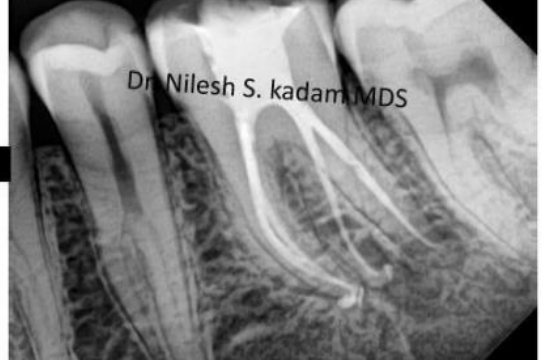

Management of Radix Entomolaris…. A Case Report.

Dr. Nilesh S. Kadam MDS (Micro-Endodontist) Introduction: To achieve success in endodontics, a thorough knowledge of the dental anatomy and an understanding of the potential for variations from the norm are required.The mandibular first molar has two roots and three canals, but it can display several anatomical variations. OneOne of the several variations of mandibular...